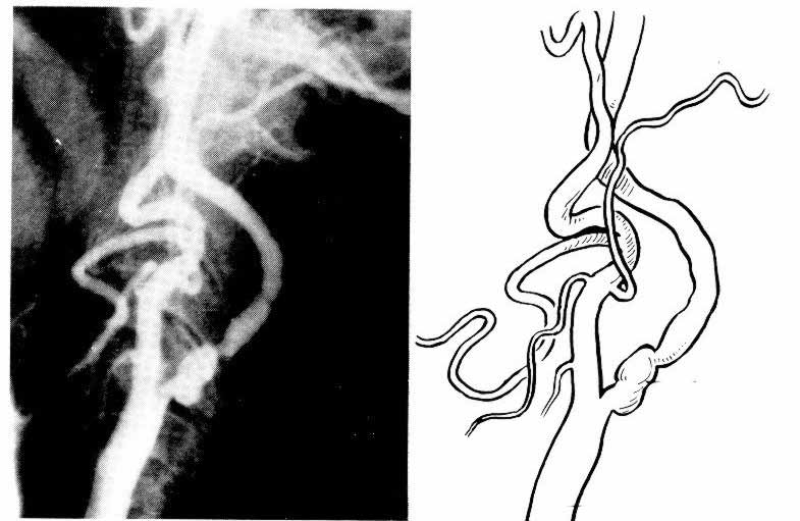

Komplikovan simptomatski karotidni plak: stenoza (80%) i ulceracija ateroslerotičnog plaka na početku unutrašnje karotidne arterije.